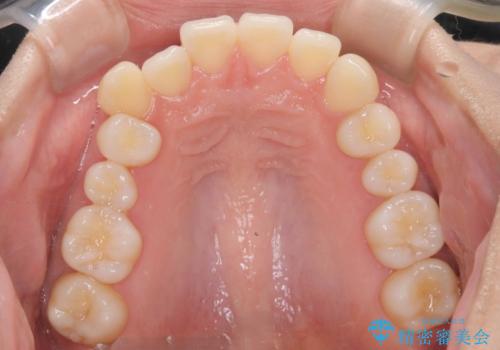

非抜歯矯正で八重歯を改善|短期間8か月で美しい歯並びに|インビザラインライト上顎のみで矯正

- 「八重歯を治したい」との主訴でご来院された患者様です。。

非抜歯で上顎のみインビザラインライトを使用して矯正を行いました。

短期間(約8か月)の治療で歯並びが整い、患者様も大変喜ばれました。